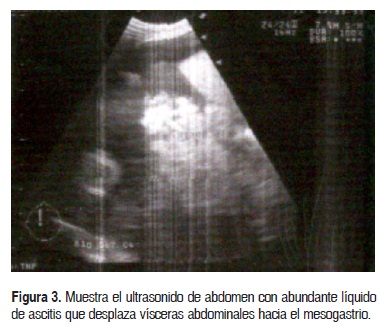

Evolucionó con apoyo ventilatorio, se detectó neumotorax anterior derecho que se manejó en forma conservadora; la radiografía de tórax mostró cardiomegalia severa (Fig. 2); el ultrasonido de abdomen mostró abundante líquido de ascitis, en el cual flotaban las visceras abdominales y desplazaba los intestinos al mesogastrio (Fig. 3); al ultrasonido transfontanelar se observó hemorragia periintraventricular grado I bilateral y ecogenicidad periventricular aumentada sin calcificaciones peri-intraventriculares o parenquimatosas.